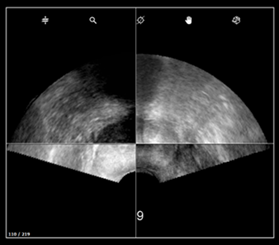

b. Prostate incomplète

- Assurez-vous que l’ensemble de la prostate soit inclus dans le Panorama.

- Qu’il y ait suffisamment de gel sur la tête de sonde

- Qu’il n’y ait pas de bulles d’air dans le protection de la sonde